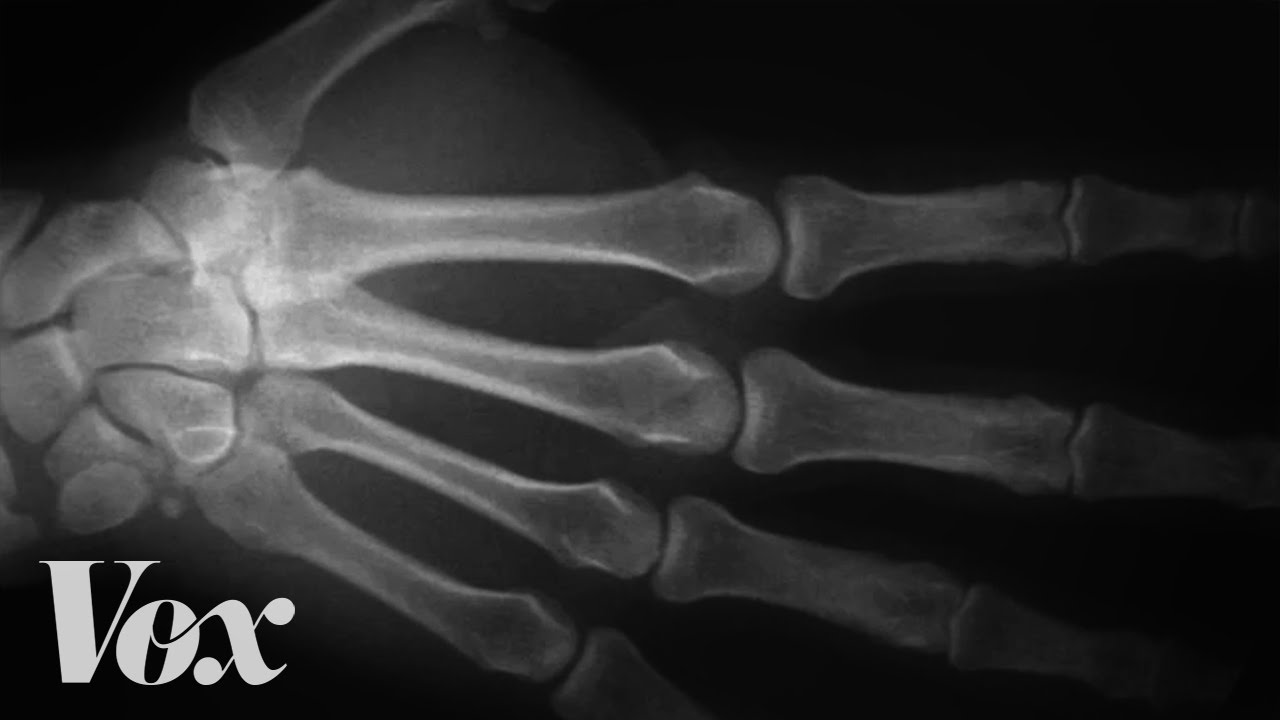

Arthritis, a condition affecting millions globally, is more than just joint pain—it’s a breakdown of cartilage that cushions bones, leading to stiffness, swelling, and discomfort. While often associated with aging, arthritis can affect people of all ages, especially after injuries. Though there’s no cure yet, treatments range from medication and physical therapy to surgical interventions like joint replacements.